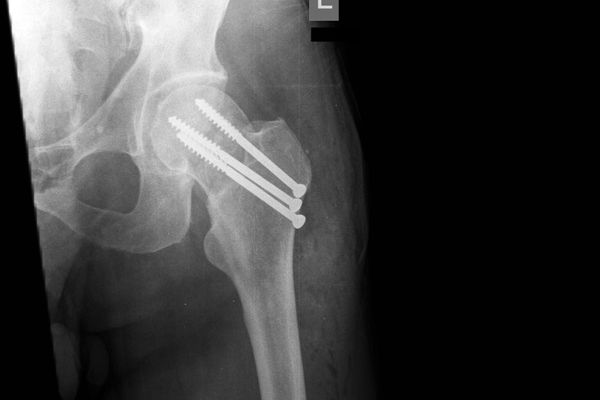

Gabinet ortopedyczny prowadzony przeze mnie specjalizuje się w leczeniu schorzeń i urazów kończyn górnych i dolnych. Zajmuję się leczeniem choroby zwyrodnieniowej stawu biodrowego i kolanowego, uszkodzeń wewnętrznych stawu kolanowego i barkowego, złamań w obrębie kończyn górnych i dolnych oraz urazów ścięgien i mięśni kończyn górnych i dolnych. Ponadto wykonuję diagnostykę USG narządu ruchu i badanie preluksacyjne (USG bioderek niemowląt). Leczę również neuropatie uciskowe kończyn (zespół kanału nadgarstka, rowka nerwu łokciowego, kanału Guyona) oraz uszkodzenia wewnętrzne stawów kończyn górnych i dolnych. Zapraszam do mojego gabinetu, gdzie dobiorę odpowiednie do schorzenia metody leczenia i zakwalifikuję do ewentualnego leczenia operacyjnego. W celu umówienia się na wizytę proszę o kontakt telefoniczny z rejestracją gabinetu ortopedycznego w Lesznie.